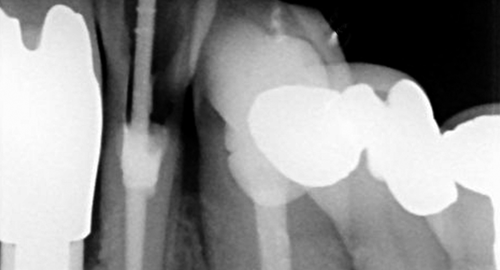

Root Canal Treatment

Also called endodontics and is required to save teeth in which the nerve has become infected.